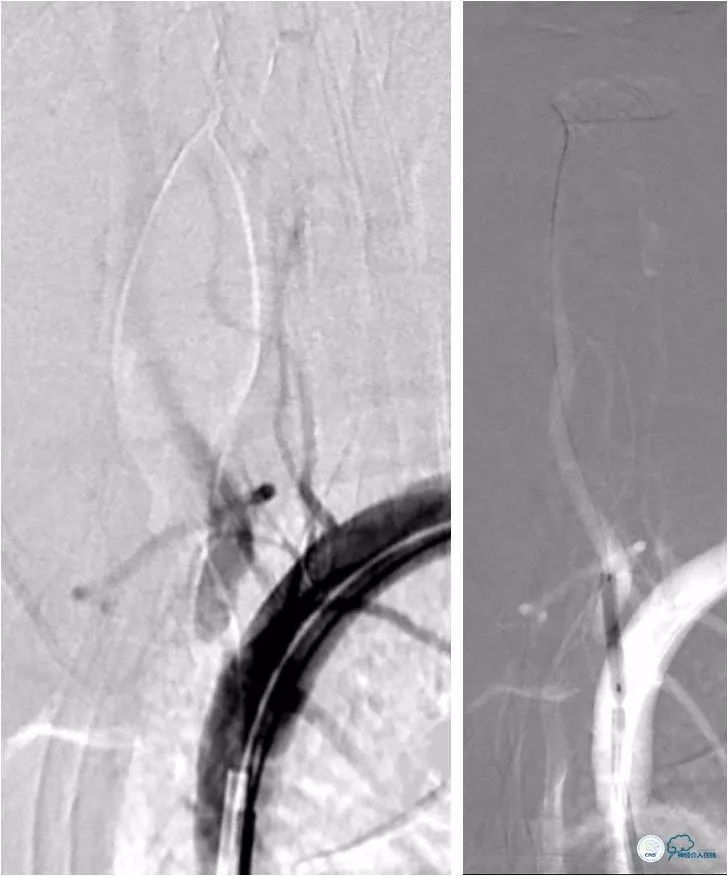

全麻下右股动脉入路,将6F导引导管至左锁骨下动脉近椎开口处, Transend微导丝(0.014″,300cm)放置于左椎动脉V2段,先用Ultra soft SV球囊(3×20mm)预扩张病变(图10)。

图10

其后置入Blue球扩支架(5×15mm),再跟进导引导管至左椎动脉V2段(图11)。

图11

此时造影示基底动脉重度狭窄(12)。

图12